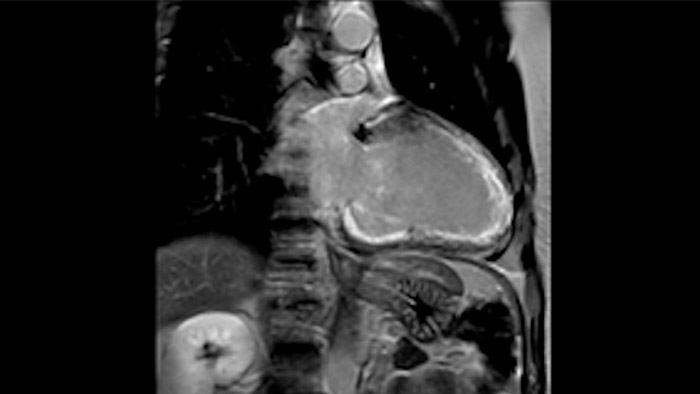

Diagnostic and prognostic utility of cardiac MR is increasing. Assess the anatomy and function of the heart using cine acquisitions, acquire information about perfusion and viability of the cardiac tissue, visualise potential edema with black blood sequence, access and even quantify tissue characterisation with CardiacQuant.

Strengthening clinical confidence and cardiac imaging efficiency In this webinar, Prof. Sebastian Kelle and Prof. Raman Danrad are sharing their experiences utilising a 1.5T MR system and spectral CT for improved cardiac imaging. They are also discussing the perspectives on the current impact of COVID-19 and talk about new clinical guidance for managing the disease into its post acute phase.